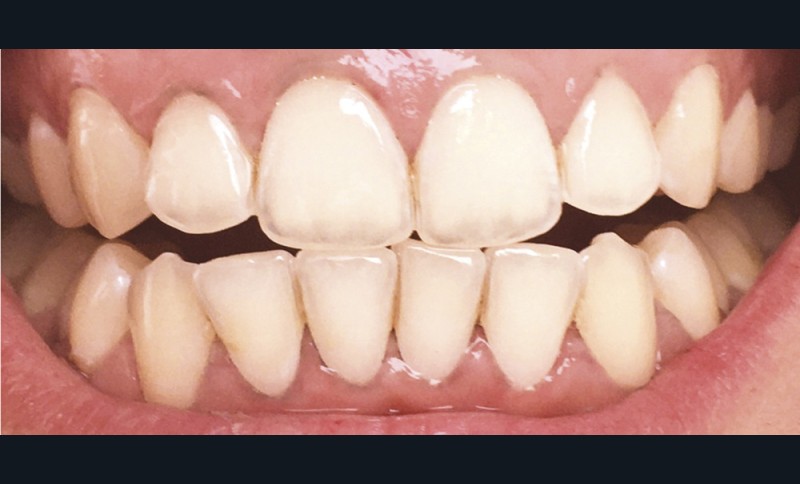

Les modifications hormonales à mettre en relation avec l’hygiène bucco-dentaire, les paramètres socio-économiques, l’âge précoce de la grossesse ainsi que l’augmentation du grignotage pourraient augmenter la prévalence des caries dentaires chez la femme enceinte. Ces patientes sont régulièrement sujettes à des envies multipliant le nombre de prises alimentaires souvent très riches en sucre. Ces apports sucrés, associés à la baisse du pH salivaire lors de la grossesse, entraînent un déséquilibre du cycle déminéralisation et de reminéralisation. Le risque carieux peut être augmenté, ainsi que la susceptibilité à l’érosion dentaire accrue par les vomissements et/ou les reflux gastro-œsophagiens [2]. L’action hormonale peut également avoir des répercussions sur les tissus parodontaux. La gingivite gravidique observée sur plus d’une femme enceinte sur deux, constitue une réponse inflammatoire de la gencive exacerbée par la présence de plaque bactérienne, et favorisée par l’augmentation des taux d’œstrogène et de progestérone [3] (fig. 1). 5 % des futures mères développeront un épulis, dont l’étiologie reste méconnue (fig. 2) [4].

Lorsque l’on consulte les sites internet, il n’existe pas de consensus quant à la technique de son utilisation. Il est généralement conseillé de frotter du citron directement sur les dents (fig. 4), ou de tremper sa brosse à dents dans du jus de citron pur et d’effectuer son brossage. Certains « tutoriels » préconisent d’utiliser ce jus ou de l’eau citronnée comme bains de bouche ! Toutes ces stratégies pour « blanchir » les dents font appel à l’acide citrique contenu dans le citron. Cet acide est l’un des composants les plus présents dans les sodas et autres boissons acides. Si les consommateurs connaissent l’effet néfaste de ces boissons sur leurs dents, ils ne font malheureusement pas le rapprochement avec le citron, un fruit, forcément bon pour la santé. Malgré un grand nombre d’études démontrant les effets nocifs érosifs du citron sur les dents définitives comme sur les dents temporaires, ces pratiques continuent à être couramment utilisées [11].

Le processus d’érosion peut être divisé en deux étapes. La première est une déminéralisation partielle. À ce stade, une reminéralisation reste possible car de l’émail déminéralisé subsiste et des ions, calciums, phosphates ou du fluor, peuvent encore s’y fixer. Quand l’utilisation d’un acide devient trop fréquente par rapport aux processus de reminéralisation, les couches superficielles d’émail fragilisées à l’occasion de la première étape sont éliminées. La perte de substance est alors irréversible (fig. 5). Après la perte de l’émail, celle de la dentine sera plus rapide du fait de sa moindre minéralisation [12]. Ces lésions peuvent entraîner des sensibilités difficiles à éradiquer et créer un déficit esthétique, à l’opposé de l’effet recherché initialement. Les effets déminéralisants de l’acide citrique, rendraient la dent plus sensible aux lésions d’abrasion et d’attrition, augmentant d’autant plus la perte de substance [14].

Le biofilm qui se reforme en quelques minutes après le brossage, protège contre l’érosion en agissant comme une barrière de diffusion ou une membrane à perméabilité sélective limitant le contact direct entre et la surface de la dent et les acides [13]. L’action de frotter du citron ou d’en imbiber sa brosse à dents réduit ou supprime l’épaisseur de la pellicule, compromettant ainsi ses propriétés protectrices. Un brossage réalisé juste avant l’application d’acide citrique est donc délétère. Il en est de même immédiatement après, car cela va éliminer l’émail préalablement déminéralisé par le citron.

Des études [15, 16] de l’état de santé bucco-dentaire tendent à montrer que la prévalence de l’érosion dentaire a augmenté dans les pays industrialisés, alors que celle des lésions carieuses a diminué de façon constante au cours de ces quarante dernières années. Ces érosions, que nous diagnostiquons de plus en plus souvent chez nos jeunes patients, pourraient devenir un problème de santé publique.